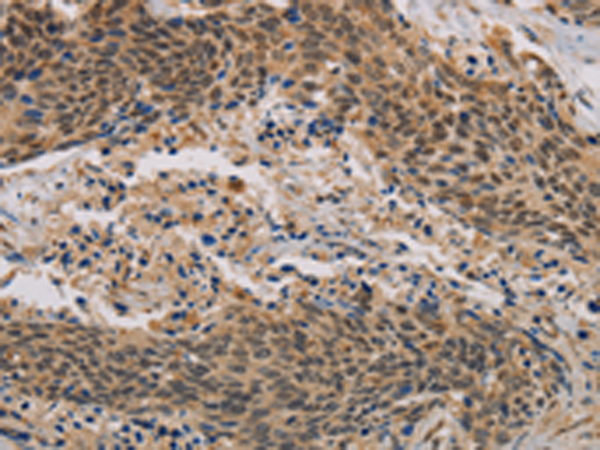

分类: 科研抗体货号: P10761别名: KACL; PILAR; UNQ5792应用: IHC反应种属: Human